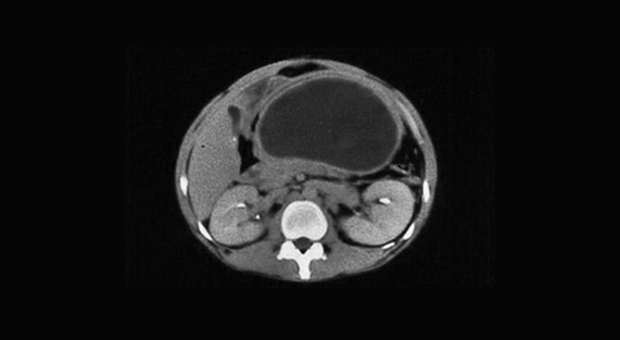

Иллюстрация №3: Компьютерная томография при хроническом панкреатите

Диагноз основывается на анамнезе и подтверждается визуализирующими исследованиями и лабораторными тестами, оценивающими структуру и функцию поджелудочной железы (рис. 2, 3) [9].

Амилаза и липаза сыворотки может соответствовать норме или быть незначительно повышена. У 5-10 % пациентов с хроническим панкреатитом компрессия дистальной части общего желчного протока ведет к увеличению билирубина сыворотки и щелочной фосфотазы. Мальабсорбция жира ведет к увеличению его экскреции с калом (более 7 грамм в день). Выявление панкреатических кальцификатов при рентгенографии, УЗИ или компьютерной томографии является диагностическим критерием хронического панкреатита. Эти кальцификаты обнаруживаются в примерно 25-60 % всех случаев хронического алкогольного панкреатита и у 35-80 % пациентов с панкреатитом другой этиологии. Компьютерная томография может также выявить локальное увеличение размеров поджелудочной железы, ее атрофию, расширение панкреатического протока или псевдокисту. РХПГ является наиболее чувствительным и специфическим визуализирующим исследованием в диагностике хронического панкреатита (рис. 3).